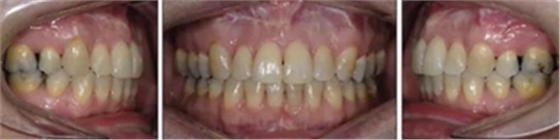

患者曾行正畸治療,現(xiàn)覺笑容不美觀前來就診。患者正面觀及側(cè)貌示下頜發(fā)育不足,偏高角,唇閉合不全。上下頜中線齊。覆合、覆蓋4毫米。磨牙關(guān)系及尖牙關(guān)系II類。上頜擁擠度4mm,下頜擁擠度6mm。4顆第一前磨牙在第一次正畸治療時已拔除。上下牙弓呈尖圓型,牙弓狹窄。

治療結(jié)果:

患者側(cè)貌改善,下唇唇肌緊張消失,上下唇可自然閉合。磨牙及尖牙關(guān)系糾正至I類,覆合覆蓋正常。上下頜弓型糾正至卵圓形,牙弓寬度增加。頭影測量分析示SNA角81.8°,ANB角3°。頭影測量重疊圖示下頜骨向后旋轉(zhuǎn),垂直面高度略有增加。